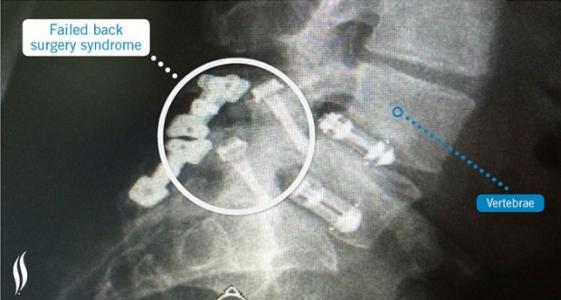

On estime que le syndrome post-laminectomie ou FBSS (Failed Back Surgery Syndrome) touche environ 40% des patients souffrant de lombalgie et ayant subi une chirurgie de la colonne vertébrale. Cette étude de l’Université du Vermont, montre l’association considérable entre le FBSS et la fibromyalgie : environ un patient sur 4 souffrant de ce syndrome post-chirurgie rachidienne reçoit un diagnostic de fibromyalgie. Et ces patients doublement atteints sont en général ceux qui ont subi le plus grand nombre d’interventions. Un appel aussi à bien évaluer l’option chirurgicale chez les patients fibromyalgiques.

Après chirurgie rachidienne pour prise en charge d'une lombalgie, certains patients vont éprouver des douleurs chroniques : Le syndrome post-laminectomie ou FBSS (Failed Back Surgery Syndrome) décrit ainsi l'état de ces patients aux résultats infructueux après une chirurgie de la colonne vertébrale pour traiter les maux de dos. De plus le taux de succès d'une chirurgie rachidienne diminuant avec les interventions, l'incidence du FBSS augmente donc en conséquence. On estime que jusqu'à 40% des patients qui subissent une chirurgie à dos ouvert souffriront de ce syndrome. Le FBSS tend va toucher plus particulièrement la région lombaire (inférieure) et moins souvent la région cervicale (supérieure) de la colonne vertébrale. Ici, les auteurs estiment, au-delà de l'invalidité et de la diminution de la qualité de vie, l''impact économique de la FBSS de 30.000 à 40 000 € par patient. Etant donnés les taux croissants de chirurgie lombaire et les taux d'échec élevés, l'équipe a cherché à mieux identifier les patients atteints de fibromyalgie avant la chirurgie pour pouvoir les éduquer à la gestion des symptômes. Fibromyalgie et chirurgie orthopédique : Plusieurs études ont montré que les patients atteints de fibromyalgie connaissent moins d'amélioration dans les scores de douleur après procédures orthopédiques comme le remplacement du genou ou de la hanche, cette étude confirme que c'est également le cas après une chirurgie du dos : l'étude, qui a porté sur l'ensemble des patients suivis au Centre médical de l'Université du Vermont de 2010 à 2015, montre en effet une association entre la fibromyalgie et le FBSS très significative avec donc 25% des patients atteints de FBSS ayant un diagnostic de fibromyalgie (voir visuel ci-contre) vs 1,75% en population générale (Source PLoS ONE (1)). Les chercheurs ont quantifié pour chaque patient le nombre total de chirurgies et classé les procédures chirurgicales selon le type.